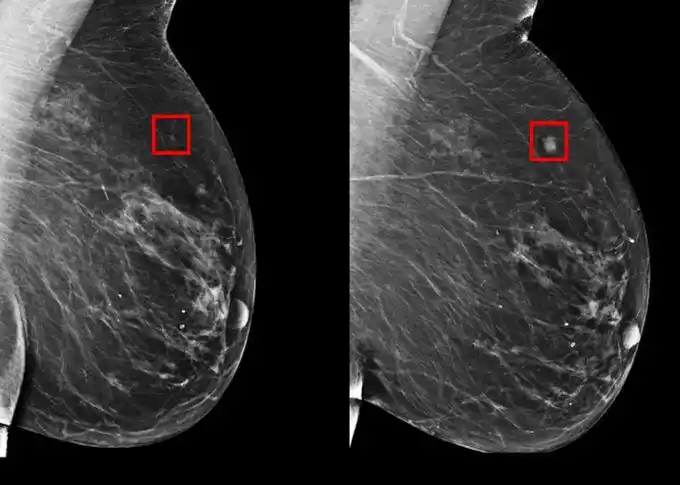

Utilizando Inteligencia Artificial (IA), investigadores del Hospital General de Massachusetts desarrollaron un modelo para predecir el cáncer de mama hasta cinco años antes de que se manifieste.

Los investigadores probaron la tecnología con datos de 2009 a 2022 provenientes de 90,000 mamografías de más de 6,000 pacientes del Hospital General de Massachusetts.

El sistema de inteligencia artificial pudo detectar patrones sutiles que no podían ser identificados por humanos en los tejidos mamarios, logrando prever las posibilidades del desarrollo del cáncer.

La inteligencia artificial predijo el 31% de los casos de pacientes de alto riesgo, lo que representa una mejora significativa en la prevención de la enfermedad, ya que las técnicas tradicionales anteriores solo podían predecir el 18% de estos casos.